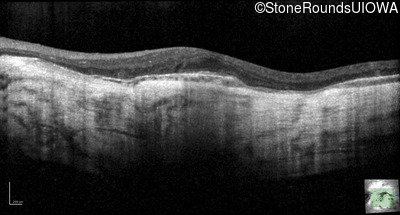

Optical Coherence Tomography - Left - 20/25 +2

Exemplar / OCT Stack